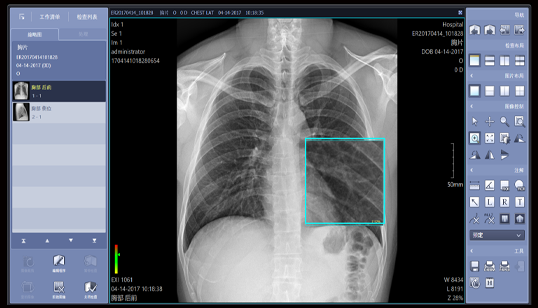

胸片不同尺寸对比

影像清晰,细节突出,无伪影

图像智能白平衡功能

自动组织均衡技术

自动虚拟电离室技术

超精细细节显示

影像智能调节

多角度测量

• 多种测量工具

影像操作

• 黑白反转图像、图像旋转、图像比较

无损处理

• 局部游走放大功能